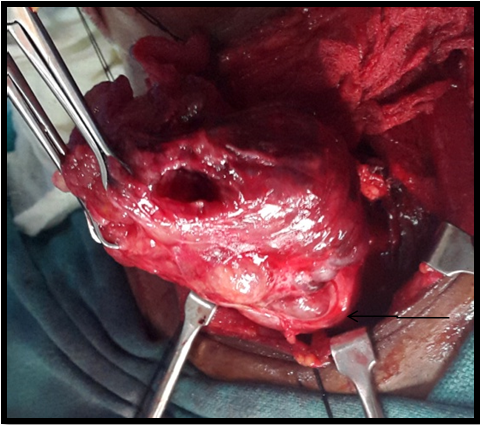

Figure 5A Multiple nodules on the surface of thyroid gland (arrow). Both the lobes dissected out after preserving parathyroid’s and RLN.

Figure 5B Retrosternal extension of the goitre visualized (arrow).